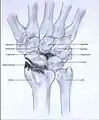

Post-traumatic osteoarthritis can be classified into four stages.[1][6] These stages are similar between SLAC and SNAC wrists. Each stage has a different treatment.

- Stage II: the osteoarthritis is localized in the entire radioscaphoid joint.

Stage II